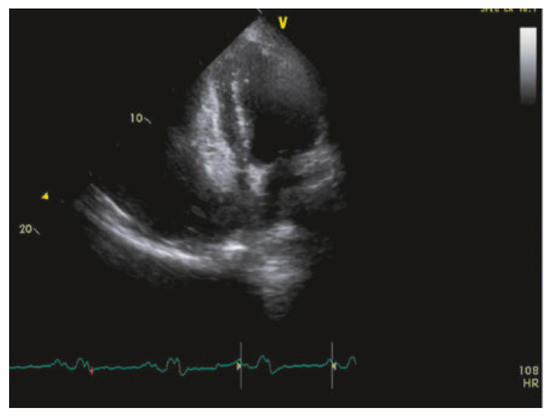

Value of Echocardiography in Differentiation of Acute Dyspnoea

by Ioannis Kapos and Felix C. Tanner

Echocardiography is one of the most effective imaging modalities for investigation of patients with acute dyspnoea. This review summarises appropriateness criteria and current guidelines for the use of cardiac ultrasound in common clinical scenarios presenting with acute dyspnoea, and illustrates such scenarios with [...] Read more.

Echocardiography is one of the most effective imaging modalities for investigation of patients with acute dyspnoea. This review summarises appropriateness criteria and current guidelines for the use of cardiac ultrasound in common clinical scenarios presenting with acute dyspnoea, and illustrates such scenarios with typical echocardiographic findings. Full article

Show Figures

Figure 1